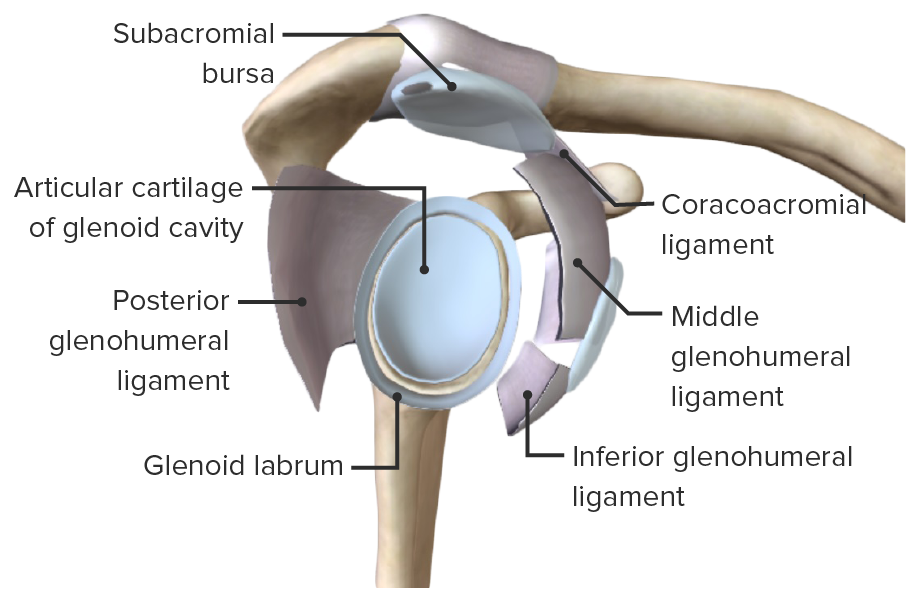

Glenohumeral ligament: анатомия и функции плечевого сустава